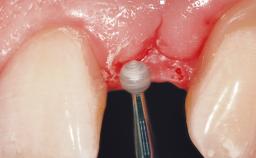

Late Placement of an Implant in a Maxillary Left Central Incisor Site

Soft Tissue Grafting Simultaneous

Bone Volume Deficient horizontally, requiring prior grafting